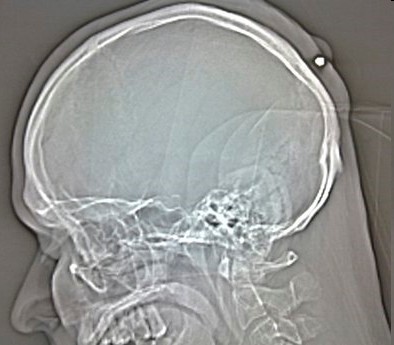

头部被子弹击中枪会什么后果?活下来的几率只有5%

头部中枪真的可以抢救过来吗?